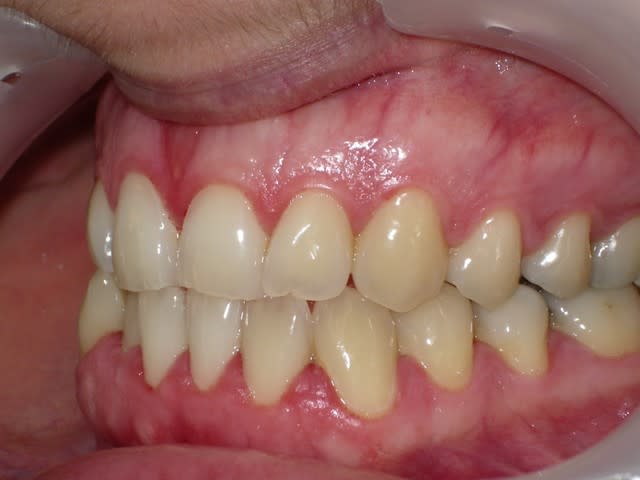

voici de la cas d'un jeune dame de 23 ans qui présente une full classe III subdivision Droite (associée à des compensations incisives de classe III), sur un terrain hyperdivergent. on note un encombrement inferieur d'environ 2 mm et une abrasion des bords triturants des incisives inf (Motif de la consultation)